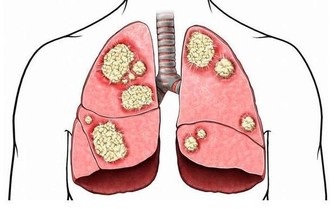

有毒表現:皮膚呈銹色,晦暗。便秘。多愁善感,容易悲傷。

排毒茶:取蒲公英葉2.0g、綠茶龍井0.8g、桂花0.2g做成蒲公英桂花茶包,每日一包,熱水代茶飲即可。

蒲公英可清火利尿,消炎殺菌,緩解咽炎;桂花止咳化痰、養聲潤肺,解除口乾舌燥、腸胃不適、除口腔異味、並可滋潤皮膚。綠茶龍井可抗氧化,抗腫瘤,抗菌、抗產物過敏, 作為日常潤肺排毒代茶飲是不錯的選擇!